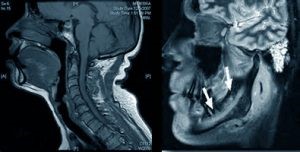

Увидеть в деталях форму и положение внутреннего и наружного полюсов головок височно-нижнечелюстного сустава (ВНЧС) позволяет МРТ челюсти. Это обследование проводят в клиниках и диагностических центрах на специальном ультрасовременном оборудовании. Метод является полностью безопасным для здоровья и не вызывает каких-либо побочных эффектов. Благодаря томографии ВНЧС можно вовремя выявить все имеющиеся патологические изменения в мягких и костных тканях нижней и верхней челюсти.

МРТ является одним из методов диагностического исследования, позволяющим рассмотреть структуру сустава, который расположен между височной костью и нижней челюстью. В силу анатомических особенностей, данная часть тела является сложно диагностируемой. Однако благодаря МРТ челюсти можно получить полноценную картину ее состояния.

МРТ позволяет врачу выявить характер заболевания и составить оптимальную схему дальнейшего лечения пациента. В ходе проведения данной процедуры можно увидеть в деталях:

- Костную структуру сустава.

- Хрящевые элементы.

- Околосуставные мягкие ткани.

В основе КТ находится технология послойного сканирования диагностируемых участков лицевой области. В результате врач-рентгенолог получает трехмерное изображение высокого качества, на котором можно рассмотреть все детали структуры суставов и челюсти, а затем выявить даже самые незначительные изменения в их строении.